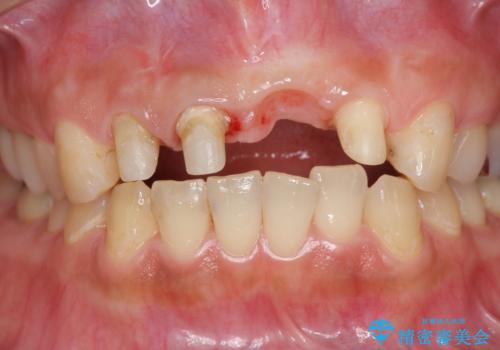

左側の前歯には他院で埋入されたポジションの悪いインプラント補綴により歯冠長の長いクラウンが装着されており、感染による排膿も認められこのまま審美性を改善するのは難しい状態です。

不良インプラントを除去し最終的にブリッジによる補綴で審美性の改善を行うこと、その準備として骨の造成・歯肉の移植による歯の欠損部顎堤のボリュームを維持・増大を計画します。

感染したインプラントからは排膿が間欠的に認められ、掻爬・除去が検討されうるような状況でした。

より審美的な改善を強く求められたため、インプラントを除去し可及的に欠損部顎堤を増大したのちブリッジによる審美改善を行いました。